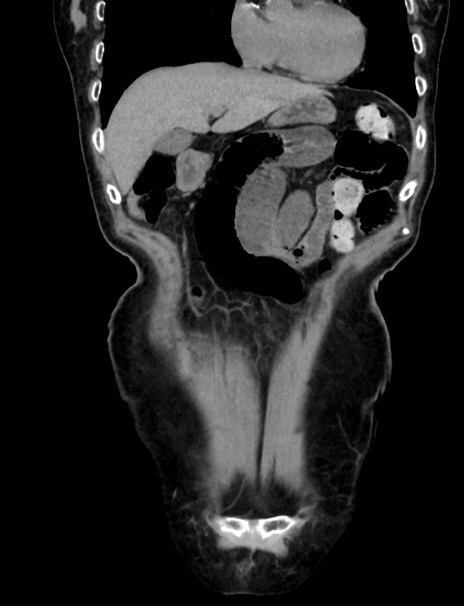

症例33(冠状断像)

【症例】70歳代 女性

【主訴】心窩部痛

【現病歴】延髄病変の精査・加療にて神経内科入院中。本日より心窩部痛あり。

【身体所見】右下腹部を中心に圧痛と反跳痛あり。

【データ】WBC 10900、CRP 0.02